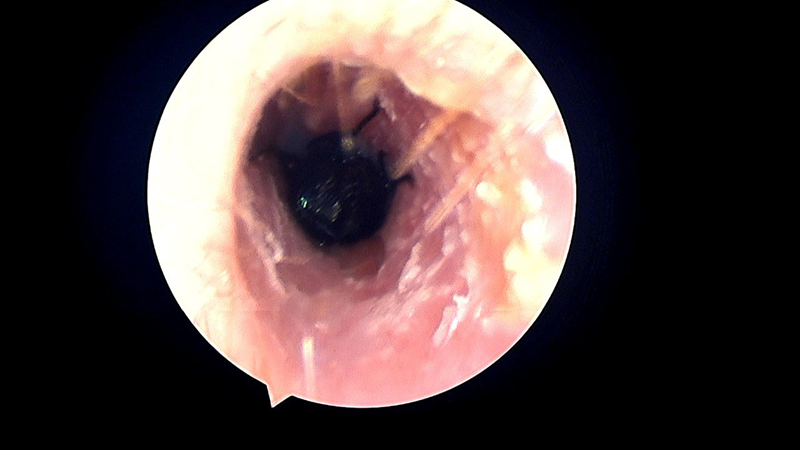

Qua thăm khám lâm sàng và nội soi tai mũi họng, bác sĩ phát hiện trong tai trái bệnh nhân có dị vật là côn trùng còn sống. Ngay lập tức, bác sĩ đã xịt thuốc gây tê làm bất động côn trùng, sau đó khéo léo sử dụng dụng cụ chuyên dụng gắp ra ngoài. Dị vật được xác định là một con ruồi trâu.

Hình ảnh nội soi cho thấy con ruồi trâu trong ống tai của người bệnh

Kết thúc thủ thuật, ống tai bệnh nhân nguyên vẹn, không chảy máu, không ảnh hưởng đến màng nhĩ, các mảnh vụn và dịch tiết của côn trùng được loại bỏ hoàn toàn.

ThS.BS Trần Minh Dũng - chuyên khoa Tai mũi họng, Phó phòng Lâm sàng, Phòng khám Đa khoa MEDLATEC Gò Vấp cảnh báo, ruồi trâu chui vào tai rất nguy hiểm. Cấu tạo cơ thể của chúng có nhiều gai nhỏ ở chân, dễ gây trầy xước ống tai. Ngoài ra, cơ quan miệng phát triển theo dạng cắt – xé, cho phép chúng hút máu ở người và động vật, do đó có thể làm tổn thương niêm mạc, thậm chí rách màng nhĩ.